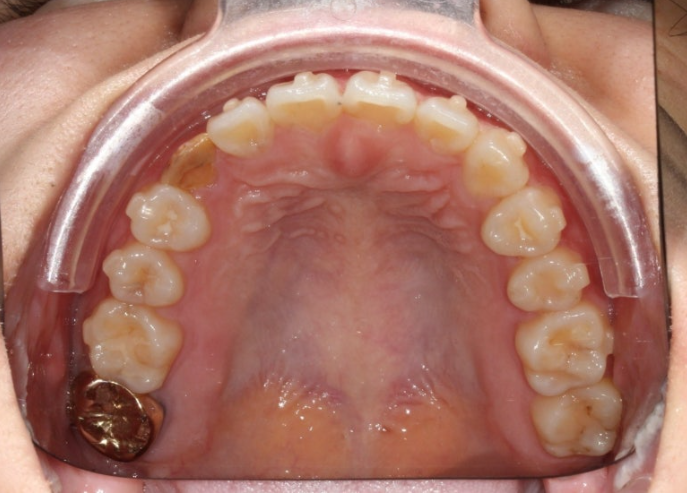

변색된 레진을 제거하고 모습을 드러낸 잔존유치 입니다. 이제 보철 준비를 해야합니다. 안정성을 위해 라미네이트 대신 크라운으로 수복하기로 합니다.

25.07

크라운 수복이 끝난 후 어태치먼트를 전부 제거하고 치료를 마쳤습니다.

어떤게 크라운이고 어떤게 자연치 송곳니인지 분간이 잘 되지 않습니다.

교합은 좋습니다.